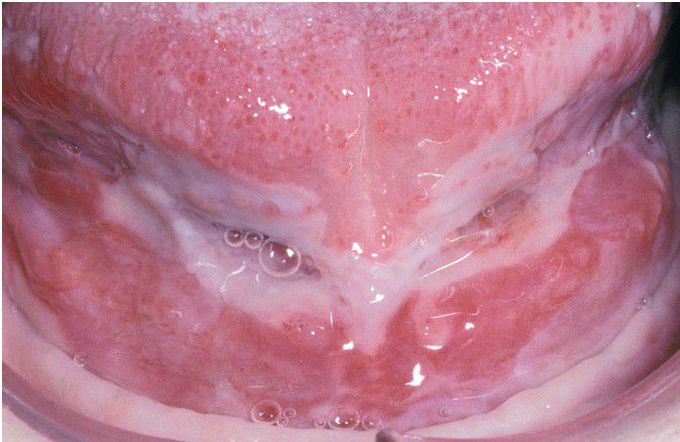

Pemphigus Vulgaris.

Large, irregularly shaped ulcerations involving the floor of the mouth and ventral tongue.